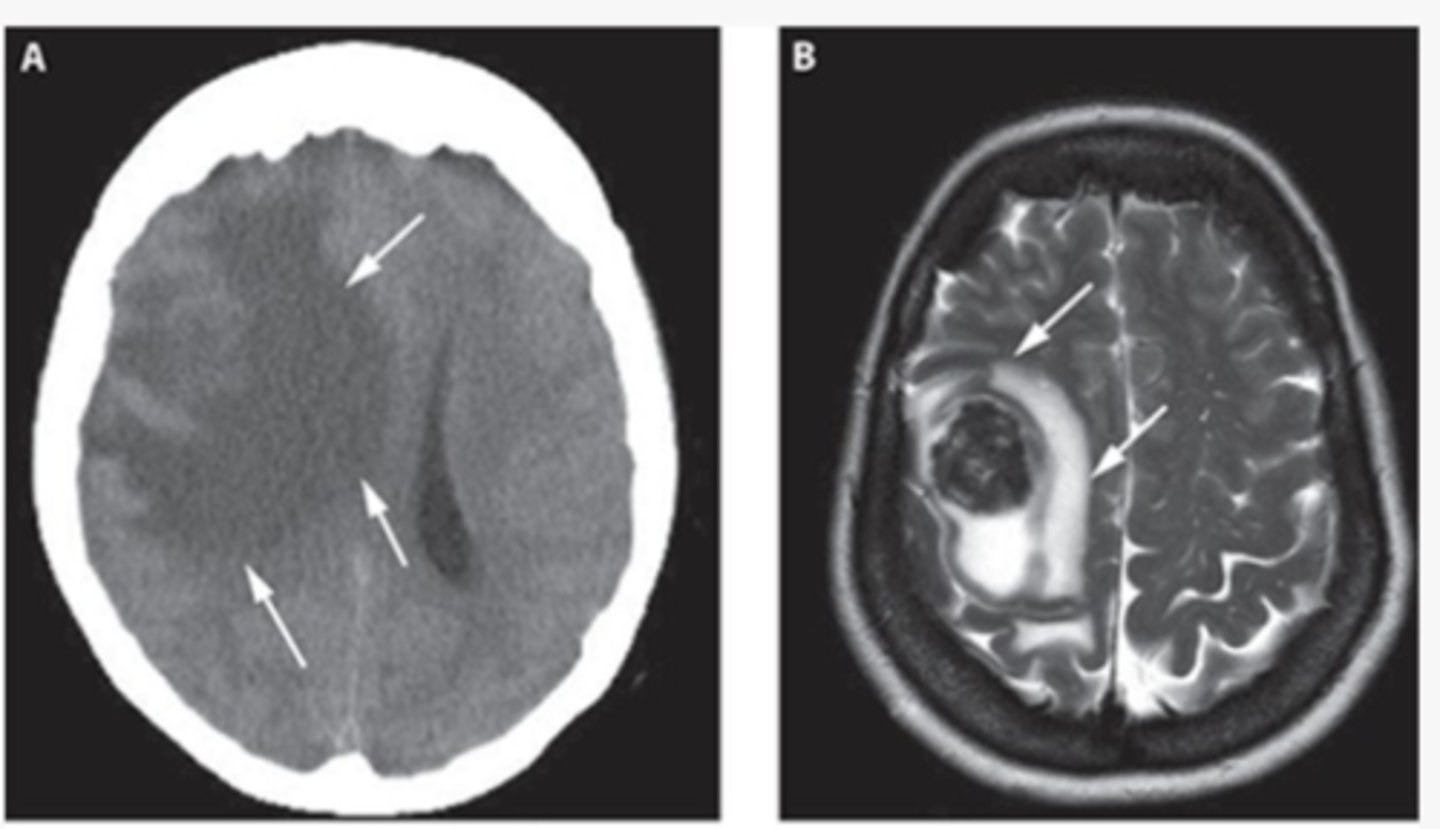

cytotoxic edema

loss of grey-white differentiation

-cant distinguish them from each other

vasogenic edema

accentuation of grey-white differentiation

-tumor or abscess

white matter appears

blacker than grey matter because it has high content of myelinated axons and lower density